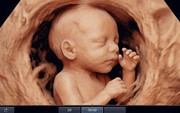

• Sản phụ khoa